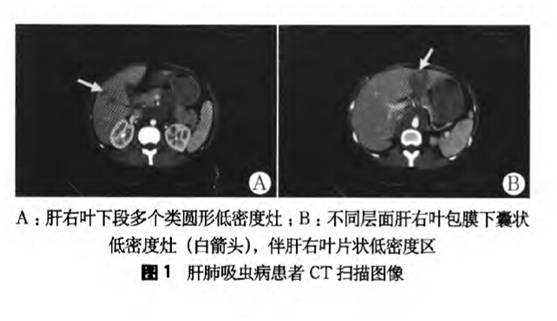

【现病史】4月前患者无明显诱因出现上腹胀痛,无发热、腹泻等不适,体质量无明显下降。到当地医院就诊, 检查结果:白细胞计数8.88×109/L;中性粒细胞百分比39.3%;血红蛋白(Hb)116 g/L;嗜酸性粒细胞计数2.94 X 109/L L;嗜酸性粒细胞百分比(EO%)33.1%;肝炎病毒标志物:抗-HBs(+),甲型肝炎和丙型肝炎抗体均为(-);肿瘤标志物(甲胎蛋白、癌胚抗原、CA-125和CAl9-9等)均未见异常;肝功能、肾功能和大小便常规均正常。B型超声示“左肝实性占位(肝癌?)”;全腹增强CT示:“肝左叶及右后叶见片状低密度影,边界不清,与相邻肝实质分界不清,增强后不均匀强化,腹膜后见不均匀囊实性软组织影,形态不规则,边界不清,增强后不均匀强化,腹腔少量积液。考虑肝内占位性病变伴腹膜后淋巴结转移(肝癌可能性大)(图1)”。

本例患者虽未进食过生的或不熟的鱼、蟹等食物,但居住在肺吸虫病发病率较高区域,血中嗜酸性粒细胞比例明显升高,仔细观察其CT表现,肝右叶和左叶内病灶为多发囊状、分叶状低密度影,囊腔内无强化,囊壁强化,符合Kim等、Rha等和王小鹏报道的肝肺吸虫病的影像学特点(图4)。